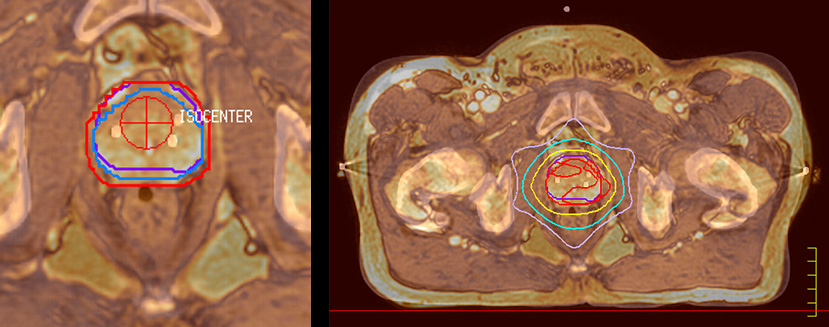

“The main reason to integrate MR imaging in RT planning is the superb soft tissue contrast that allows detailed delineation of tumors and healthy organs, which is crucial for RT planning,” says Craig W. Stevens MD, PhD.

“The good visualization is why a lot of cancer treatments can benefit from MR based treatment planning, because if we can localize a tumor better, we can aim the radiation beam at it better. This potentially allows us to shrink our margins and spare more healthy tissue.”

“Using MR, the prostate is well delineated. We quickly see the edges of cancerous tumors like in prostate cancer, and as normal structures can be defined, we can optimize the treatment plan to protect these organs and their normal function. This can potentially improve the outcome. And it improves workflow as well. We can contour more quickly, confident that the tumor is going to be in the field.”

“When a patient registers, first CT simulation and MR simulation are done, followed by CT-MR registration on Pinnacle3. Then the target and normal organ delineation is performed on MR images. Meanwhile we create a reference CT image for online treatment and localization correction. During the treatment phase we can perform additional MRI scans to visualize the anatomy changes and create an adaptive plan. This plan basically adapts the treatment plan to the changes.”

“I think that in the future functional information from MRI is going to become much more important, both for prognostic and predictive measures, as well as for treatment response measures,” Dr. Stevens concludes. “With Ingenia MR-RT we will have the ability in our department to make decisions based on, for instance, changes in blood flow and diffusion at the beginning, middle and end of treatment. I believe that over time, every large cancer center will need to have an MR scanner in their radiation oncology department.”